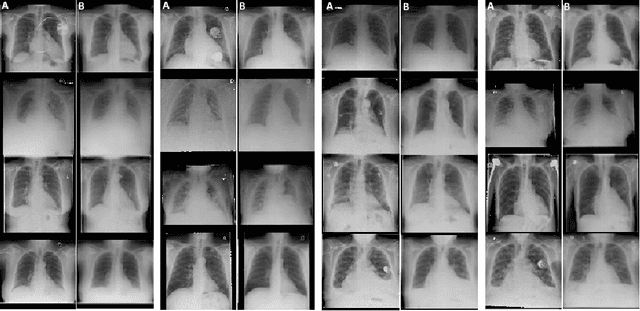

Interpretability and small labelled datasets are key issues in the practical application of deep learning, particularly in areas such as medicine. In this paper, we present a semi-supervised technique that addresses both these issues by leveraging large unlabelled datasets to encode and decode images into a dense latent representation. Using chest radiography as an example, we apply this encoder to other labelled datasets and apply simple models to the latent vectors to learn algorithms to identify heart failure. For each prediction, we generate visual rationales by optimizing a latent representation to minimize the prediction of disease while constrained by a similarity measure in image space. Decoding the resultant latent representation produces an image without apparent disease. The difference between the original decoding and the altered image forms an interpretable visual rationale for the algorithm's prediction on that image. We also apply our method to the MNIST dataset and compare the generated rationales to other techniques described in the literature.